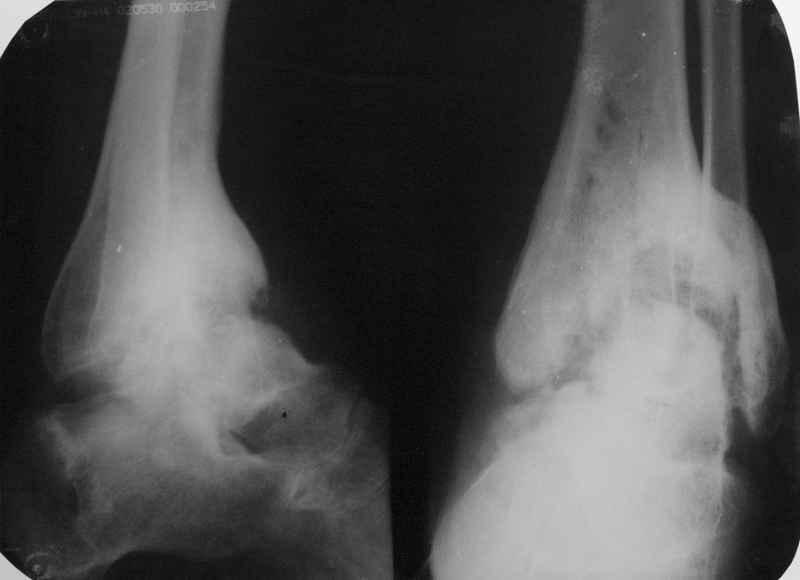

Пациентка Б. получила травму 2001 году в результате падения с высоты. За это время дважды выполнялись неудачные попытки артродезирования голеностопного сустава. Больная перед нами поставила одну задачу - восстановить опороспосонбность левой нижней конечности и только. Принято решение выполнить кейдж-артродезирование левого голеностопного сустава блокируемым интрамедуллярным гвоздем с установкой сетчатого опорного трансплантата, костной аутопластикой плюс Chronos. С целью профилактики рецидива деформации выполнили ахиллотомию (считаем, что неудачи предшествующих операций связаны с варусной тягой ахиллова сухожилия в ррезцльтате неправильно сросшегося перелома пяточной кости). На сегодняшний день - два месяца с момента операции. Пациентка перемещается в циркулярной повязке с полной нагрузкой на больную ногу.